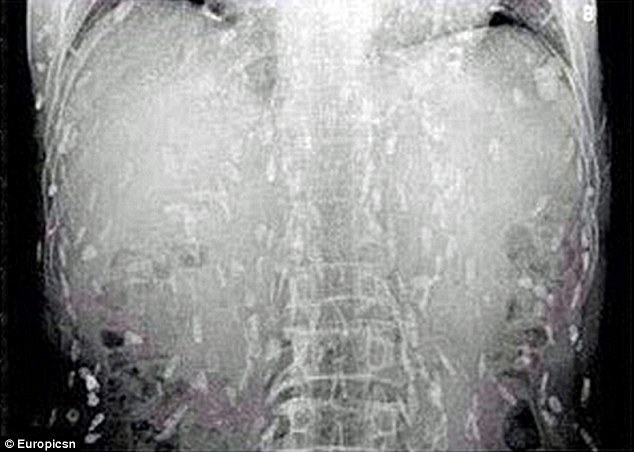

Un barbat, innebunit dupa sushi, a ajuns la spital cu trupul plin de viermi dupa ce a mancat o mancare japoneza contaminata.

Barbatul s-a dus la medic, initial, fiindca il durea stomacul si avea o iritatie pe piele. La o simpla radiogafie, medicii si-au dat seama ca trupul chinezului este infectat cu viermi.  Bietul barbat s-a ales cu acesta contaminare din cauza ca a consumat prea mult peste.